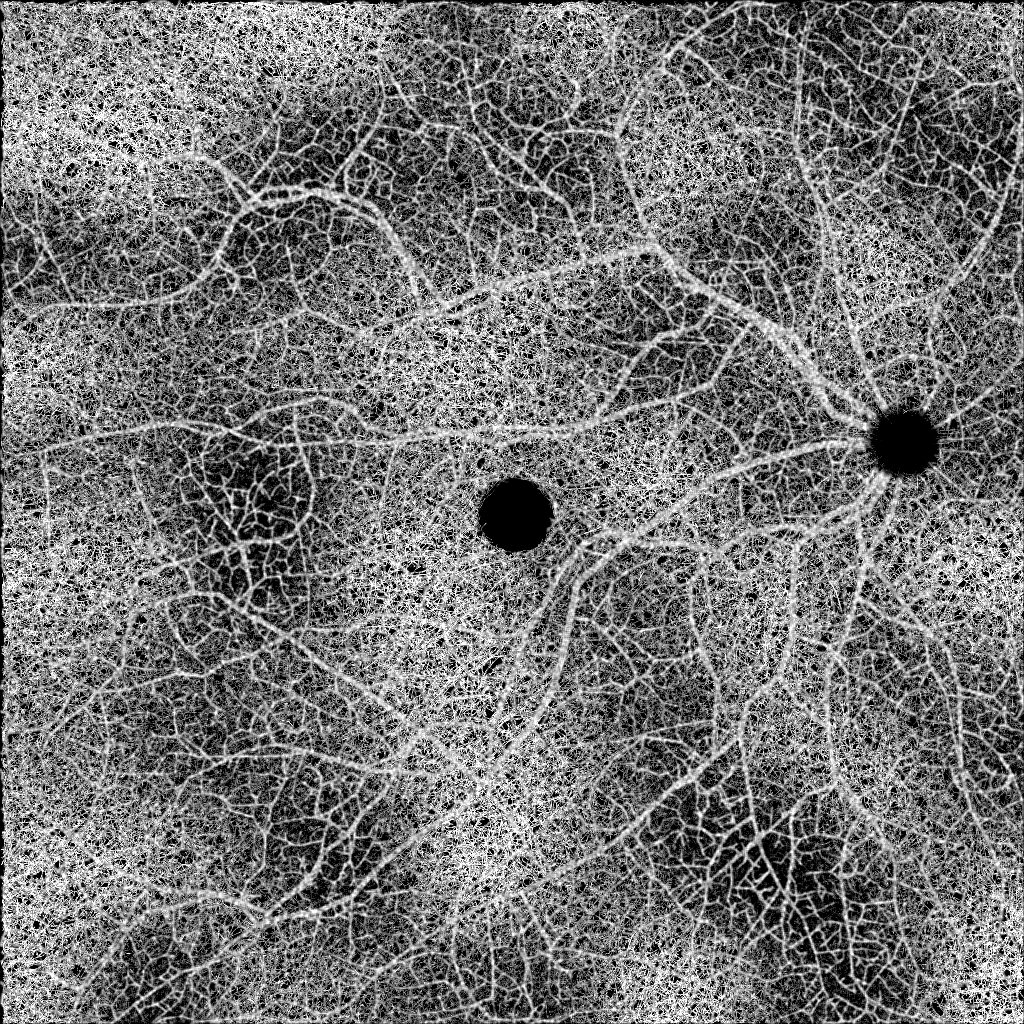

A recent survey by Sheng et al. calls OCT an “indispensable component of healthcare in ophthalmology”, but notes that there are still many problems to be solved before artificial intelligence (AI) based systems can be reliably integrated in the clinical process [3]. The Diabetic Retinopathy Analysis Challenge (DRAC) is part of MICCAI 2022 in Singapore and aims at advancing machine learning research for DR analysis on OCTA data [4]. The organizers provide three labeled datasets with more than 1,000 ultra-wide swept-source OCTA (UW-OCTA) images. The samples are pixel grayscale images and cover different field-of-views (FOVs). The challenge is divided into the tasks A) lesion segmentation, B) image quality assessment, and C) DR grading. Task A) is a pixelwise multi-label segmentation problem for identifying intraretinal microvascular abnormalities, non-perfusion areas, and neovascularization. The public training set contains 109 sample images with 86 cases of IRMA, 106 with NAs, and 35 with NVs. The training set of task B) contains 665 images, of which are graded as excellent, as good, and as poor quality images. Finally, task C) contains 611 samples where are classified as healthy, as pre-proliferative DR, and the remaining as proliferative DR (PDR). The DRAC event follows in the footsteps of similar challenges such as the Diabetic Retinopathy-Grading and Image Quality Estimation Challenge (DeepDRiD) for fundus images [5].

Diabetic retinopathy causes retinal vascular changes, and while being subtle at first, it eventually leads to dangerous vascular abnormalities and neovascularization. We hypothesize that by explicitly feeding the segmentation map of the vasculature to a deep neural network, we can provide a strong inductive bias for the network to predict the severity of DR. Recent studies suggest that early DR progression is mainly correlated with biomarkers found in the deep vascular complex (DVC), while the superficial vascular complex (SVC) is generally only affected in severe cases [1, 6]. The authors hypothesize that the DVC might be more susceptible to ischemic damage because of its anatomical proximity to the outer plexiform layer, which has a high oxygen consumption. Therefore, it becomes clear that including small capillaries in the segmentation map is vital. However, to our knowledge, there is no publicly available dataset of OCTA images with corresponding vessel segmentation that includes small capillary vessels. Merely two public datasets, namely OCTA-500 and ROSE, have been released with segmentation labels for vessels and the foveal avascular zone (FAZ), both of which unfortunately only segment the largest vessels of the SVC [7, 8]. To circumvent the problem of missing labeled data, we generate an artificial dataset ourselves. Figure 1 shows our proposed pipeline.

To bridge the domain shift from synthetic to real OCTA images, Menten et al. employ a variety of data augmentations, such as eye motion artifacts, flow projection artifacts, and changes in brightness. The background signal caused by small capillary vessels is simulated by binomial noise and convoluted by a Gaussian filter since it is computationally intractable to simulate them. After training a U-Net on a synthetic dataset, the network can extract detailed segmentation maps on real data.

Instead, we focused on testing the idea of integrating synthetic data into the prediction life cycle. We successfully extended Menten et al.’s work to generate OCTA images for ultra-wide scans. Using our training method, we can segment tiny capillaries whose diameter is similar to the physical resolution of the OCTA scanner. On this dataset, we could not find any significant improvement using the segmentation maps as input. However, we consider this finding relevant, as it indicates that the baseline models are strong enough to extract that information by themselves. It would be interesting to see whether this method could benefit from a larger image corpus, where networks are less prone to overfitting.